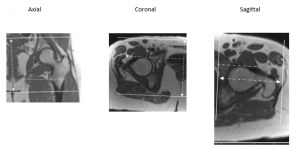

Hip

Orient axial from superior acetabulum through lesser trochanter

Orient coronal parallel to the femoral heads.

Orient sagittal perpendicular to coronal.